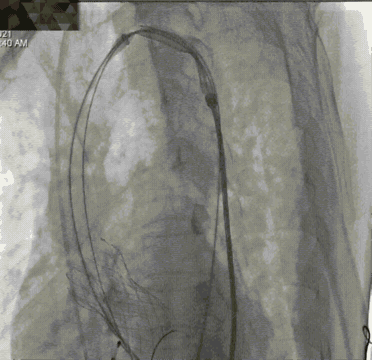

球囊后扩后,瓣膜与周围组织贴合的更好。术后即刻造影结果显示无瓣周漏,工作瓣膜形态优异。术中测量结果显示即刻跨瓣压差降至10mmHg,舒张压从术前35mmHg左右上升到60mmHg以上,术后患者症状明显改善。

球囊后扩

最终造影结果

术后即刻超声评估